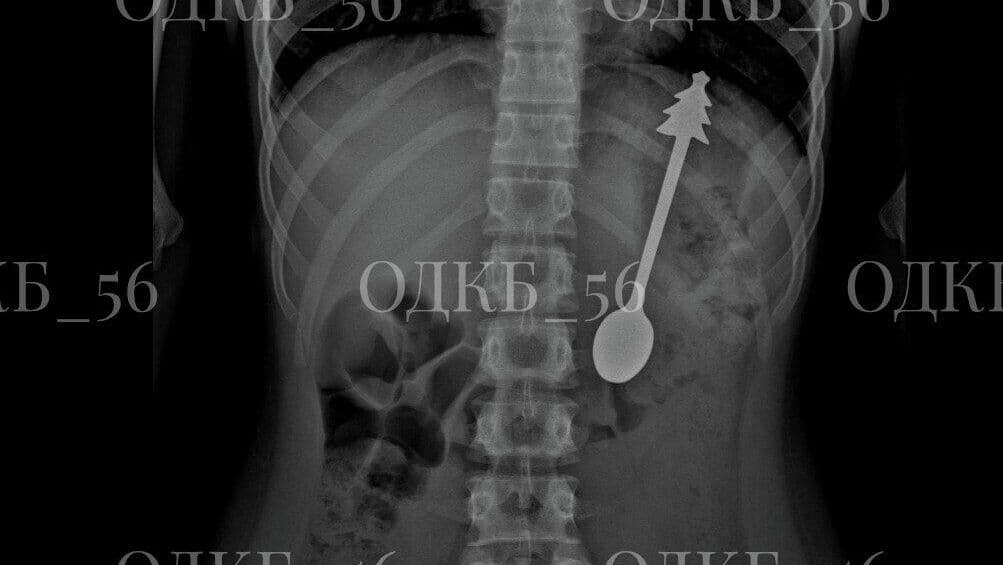

По данным областного минздрава, в детскую больницу скорая помощь привезла ребенка, который случайно проглотил ложку. Пациента срочно госпитализировали. Во время рентгенографии органов брюшной полости выяснилось, что инородное тело находится в области желудка. На опубликованных ведомством снимках рентгена видна детская ложечка, на конце ручки которой находится фигурка елки.

Ребенок в Оренбургской области проглотил 14-сантиметровую ложку

"В экстренном порядке проведено… эндоскопическое удаление инородного предмета - металлической ложки длиной 14 сантиметров. Постманипуляционный период протекал без осложнений", - говорится в сообщении.